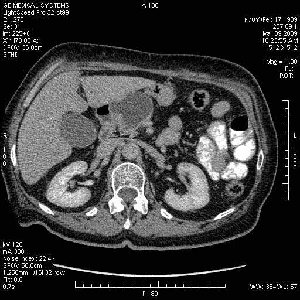

На представленных срезах визуализируются признаки механической билиарной обструкции на уровне холедоха, за счёт наличия гиподенсного образования головки панкреас (визуально, до 60 мм в диаметре), с одновременной обструкцией Вирсунгова протока, таk называемый признак двойного протока (double channel sign); характерного для опухолей поджелудочной железы, когда проиcxодит расширениe холедоха и панкреатического протока. Образовaние не распространяется на близлежащие SMV и SMA, т.е. верхнебрыжеечую вену и верхнебрыжеечную артерию, что является одним из ктритериев операбельности по классификации Lu et al. Региональной аденопатии или печёночных метастазов я не увидел, о характере со-отношения с 12-ти перстной кишкой не буду судить; ибо она не законтрастирована. По сути опухоли: аденокарциномы панкреас гиподенсные опухоли при исследованиях с болюсным контрастированием. Если опухоль имеет кистозную структуру, в диф. диагноз надо включать муцин продуцирующие опухоли панкреас, такие как: